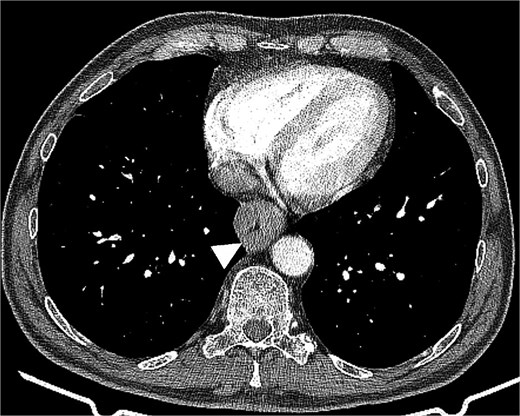

Chest and abdominal computed tomography (CT) revealed esophageal wall thickening (Fig. 1) without evidence of lymph node involvement or distant metastases. Laboratory tests, including tumor markers, were within normal ranges. A comprehensive dermatological evaluation found no signs of cutaneous melanoma or pigmented lesions. Based on these findings, the patient was diagnosed with clinical T3N0M0 primary esophageal melanoma according to the 8th edition of the Union for International Cancer Control (UICC) classification, though specific staging guidelines for this rare entity remain undefined.

Chest computed tomography revealed esophageal wall thickening up to 31 mm, resulting in significant luminal stenosis.